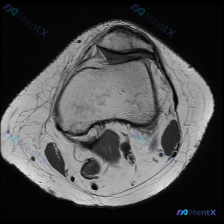

先给大家看一下这份病例的基本影像资料:这是一张膝关节MRI-T1加权序列的轴位图像,扫描层面位于股骨远端髁间窝与髌股关节层面。

影像基本信息整理

- 骨骼结构:股骨远端骨皮质、骨髓信号正常,髌骨形态完整,骨皮质连续,骨髓信号无异常;

- 关节软骨:髌骨后方关节软骨形态尚可,表面光滑,未见明显局部缺损或裂隙;

- 其他结构:关节腔无明显积液,周围肌肉、肌腱信号均匀,腘窝区域血管神经无占位,脂肪信号正常;

- 整体评估:这一特定层面未见明显急性损伤、骨性病变或解剖结构异常,髌股关节没有明确剥脱性骨软骨炎征象,股骨髁间窝结构也未见异常。